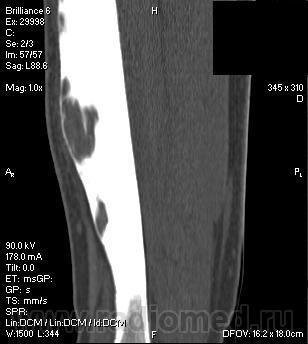

Мальчик 10 лет. Травма весной 2013 года - получил удар шайбой по голени. Периодически беспокоили боли в с/3 голени, постепенно усиливающиеся. Летом обратился за помощью, выполнены рентгенограммы, затем - КТ. Выявлена следующая картина. На настоящий момент по передней поверхности голени - отёк, болезненность, деформация. Боли беспокоят практически постоянно.

Литические очаги с массивным гиперостозом а также клиника в первую очередь наводят на мысль об остеомиелите. Но...не хотелось бы нарваться на всякие неприятные вещи вроде адамантиномы и т.д.

антекурвационная деформация голени,поражен только передний отдел большеберцовой кости.я б (если бы не видел результатов биопсии)поставил бы ОСТЕОФИБРОЗНУЮ ДИСПЛАЗИЮ. а диф диагностика-фиброзка и адамантинома. макроскопически патологическая ткань при фиброзной и остеофиброзной дисплазии очень схожи,но есть при остеофиброзке очаги оссификации(режется как по кости) если это остефиброзка-ждите рецидив(процентов 80)